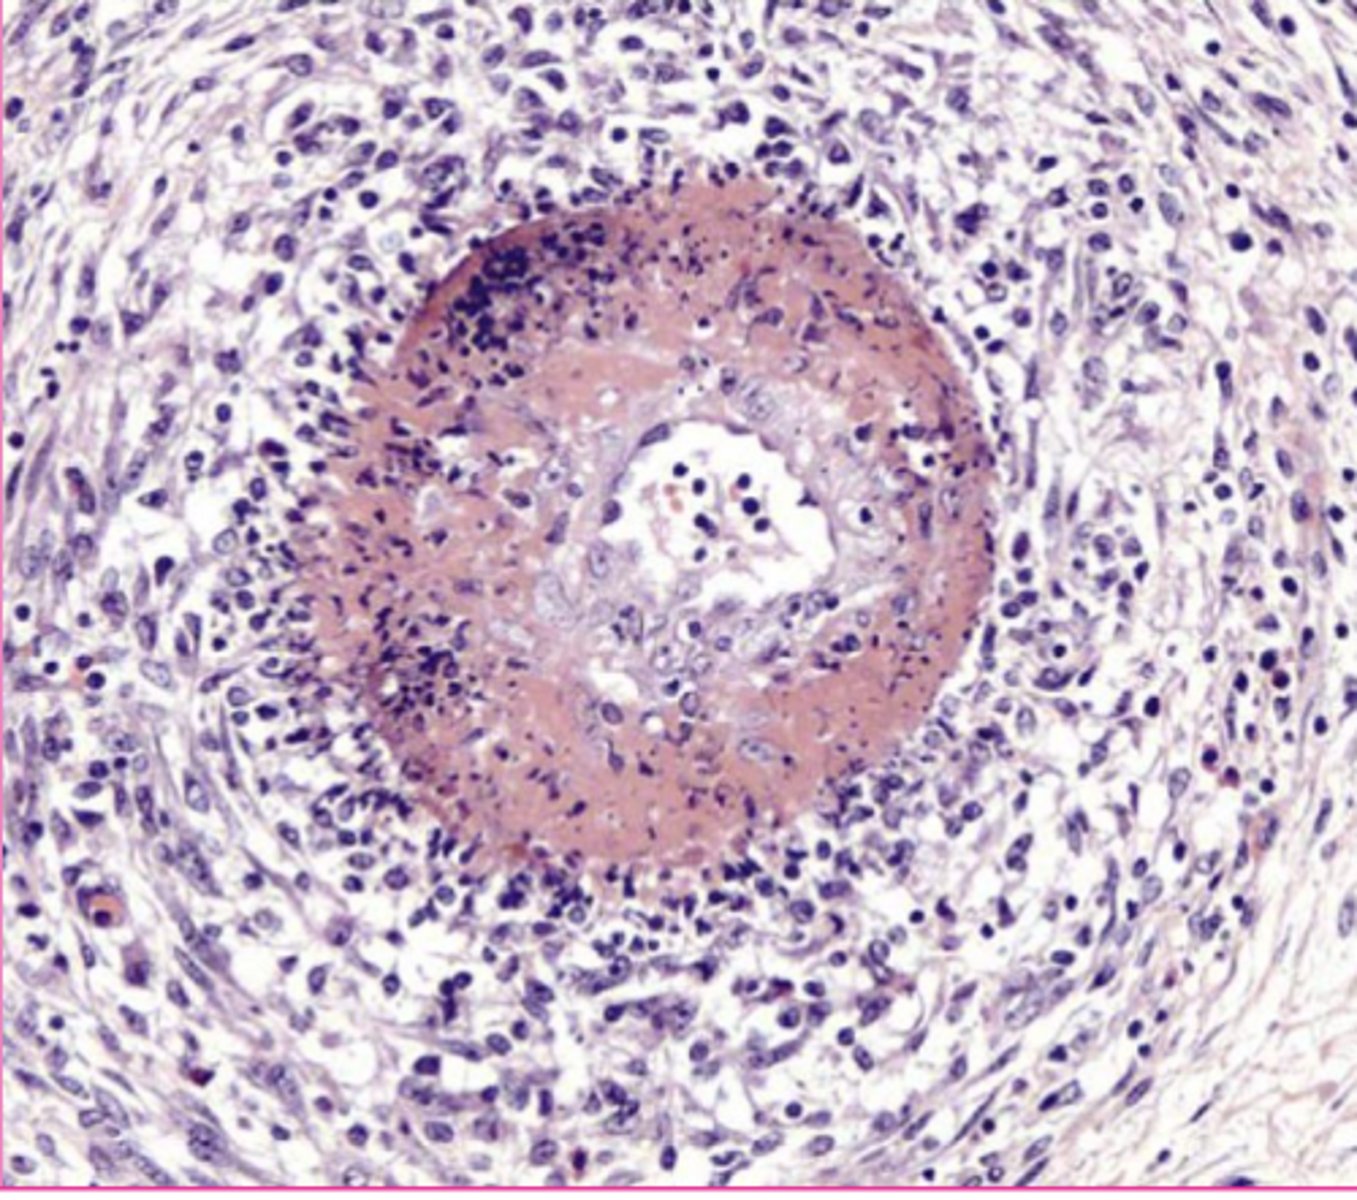

caseous

type of necrosis